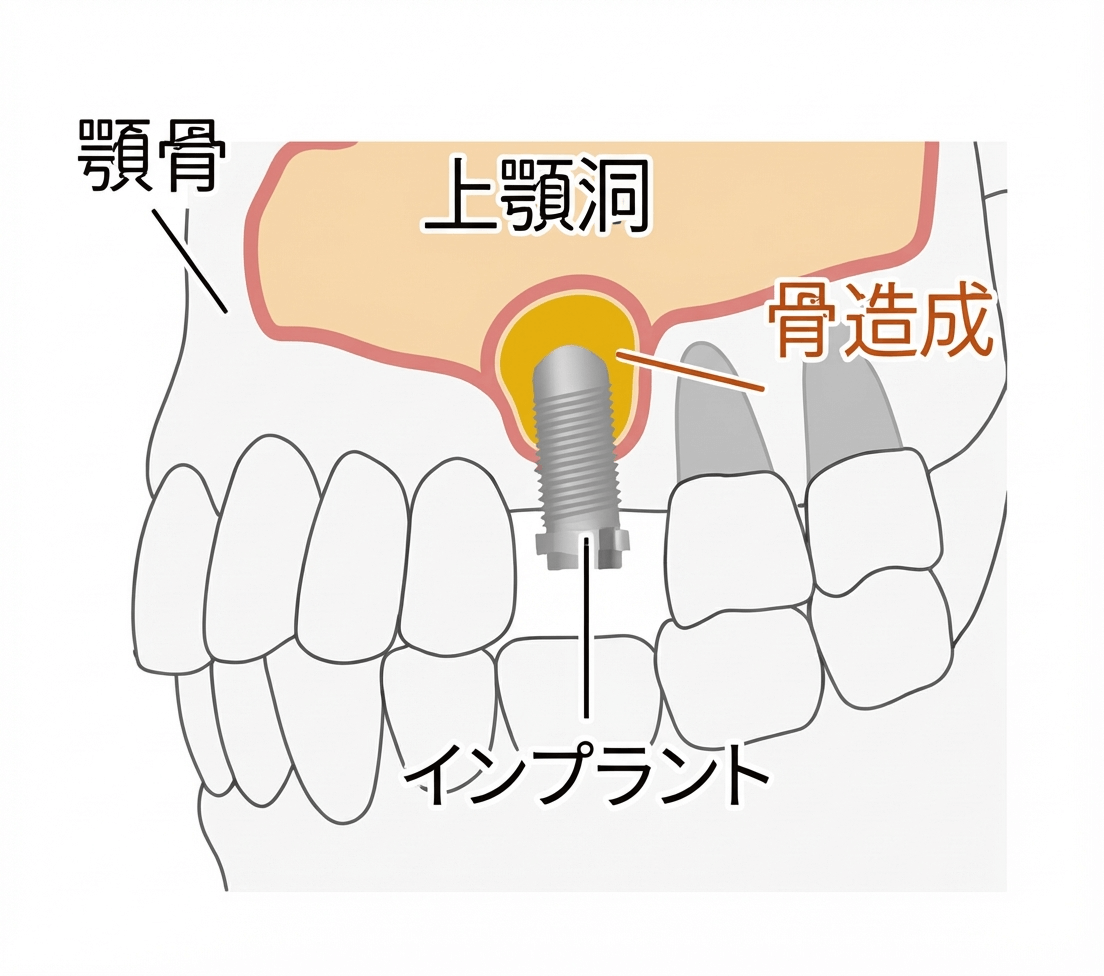

サイナスリフト

サイナスリフト(上顎洞底挙上術)は、歯科インプラント治療において上顎の骨の高さが大きく不足している場合に行われる骨造成手術の一つです。

上顎洞(鼻の横にある空洞)の底部に、歯茎の横側からアプローチし、上顎洞の粘膜(シュナイダー膜)を持ち上げ、できたスペースに自家骨や人工骨などの骨補填材を挿入します。そのため、骨の高さが極端に足りないケースや、複数の歯をまとめてインプラント治療する場合に有効です。一般的に補填した骨がしっかりと定着するまでに個人差がありますが、数ヶ月程度の待機期間が必要となるため、全体の治療期間が長くなります。当院では、CT上でのプランニングに加えて上顎骨の3Dモデルを作成し、事前シュミレーションを行い、手術の安全性をより高めています。